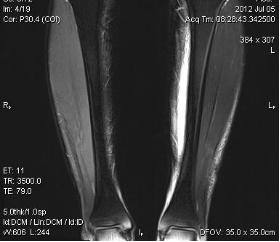

典型病例:患者,男,40岁,体能训练致左小腿肌肉撕裂伤并巨大血肿,给予脉冲磁疗、中频电疗和下肢肌肉训练指导后,血肿逐渐消退,两个月后肌肉恢复正常,继续参加训练。